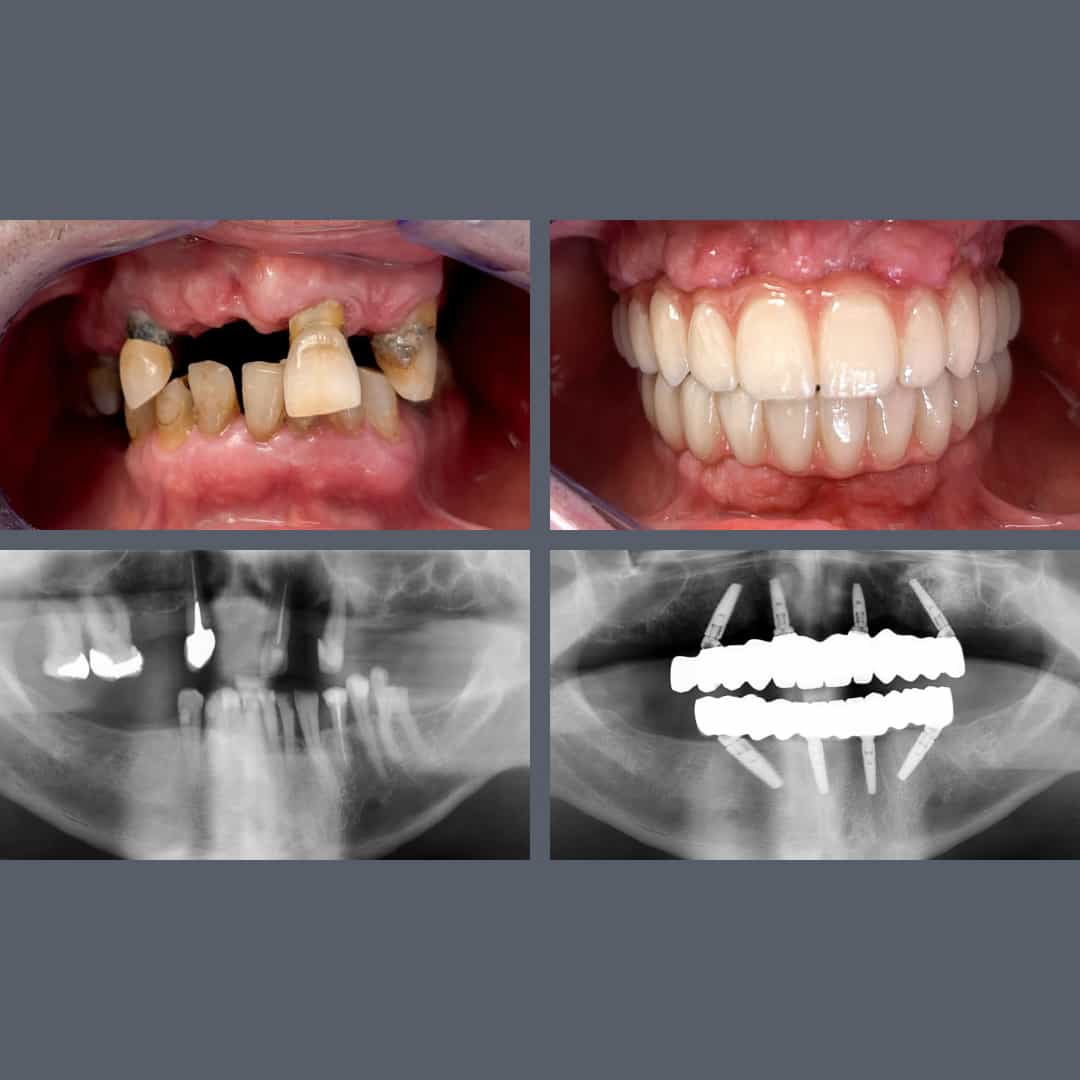

før og efter

Tandkødssygdom, uoprettelige tænder? – All-on-4®, fast protese på 48 timer